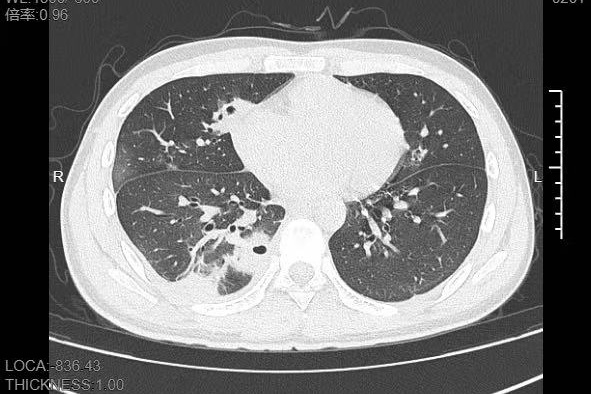

熬到第三天,小林已经烧到39℃,赶紧来到医院就诊。接诊的呼吸与危重症医学科医生一看他的症状,立刻安排了CT检查。结果显示:小林的肺里有十几个空洞,部分肺组织已经坏死,这是典型的血源性肺脓肿。

像小林这样,当细菌跑到肺组织上后,就会开始疯狂破坏肺细胞,引发局部炎症。随着炎症加重,肺组织会逐渐坏死、液化,最终形成一个个空洞。